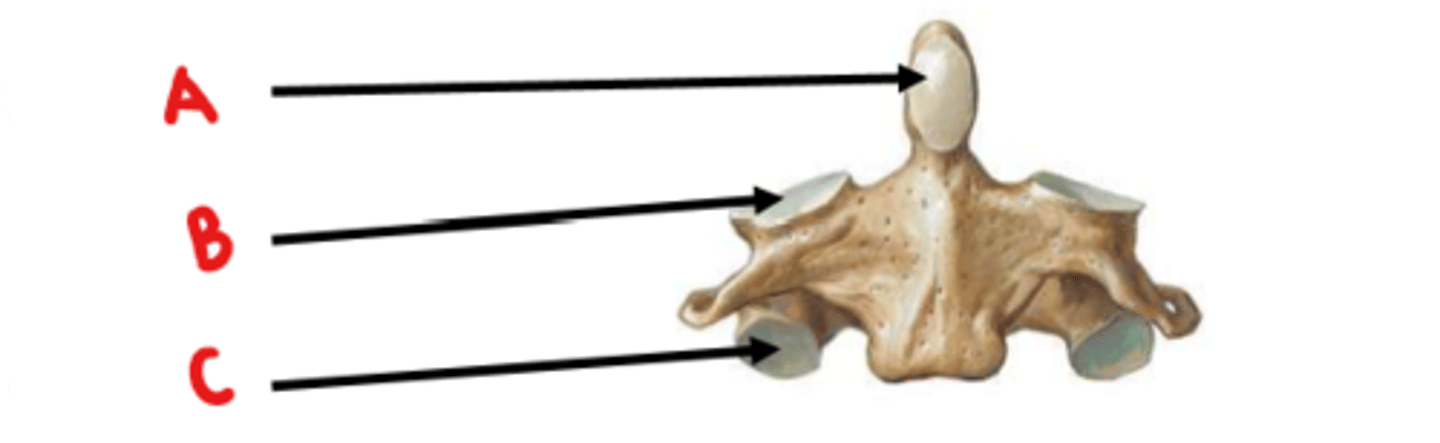

Axis (C2)

What vertebrae is this?

odontoid process (dens)

Identify A

superior articulating facet

Identify B

inferior articulating facet

Identify C